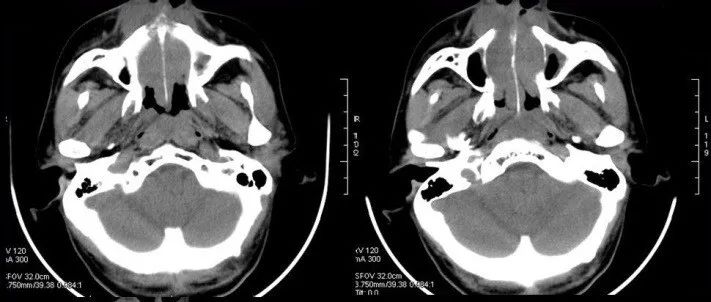

中年男性,持续性鼻塞伴右侧耳下包块10余天,请诊断!

医学影像  yxyx-app  医学影像APP,打造伴随医生快速成长的影像学习社区。与影像园(Xctmr.com)一起提供最全面的影像案例库、基础(解剖、病理、影像诊断)知识、影像技术及考题等,为医生提供最佳的医学影像参考。【所属科室】耳鼻喉科【基本资料】患者,男,59岁【主诉】持续性鼻塞伴右侧耳下包块10余天【影像图片】【讨论问题】如何诊断?【医学影像APP用户讨论】...